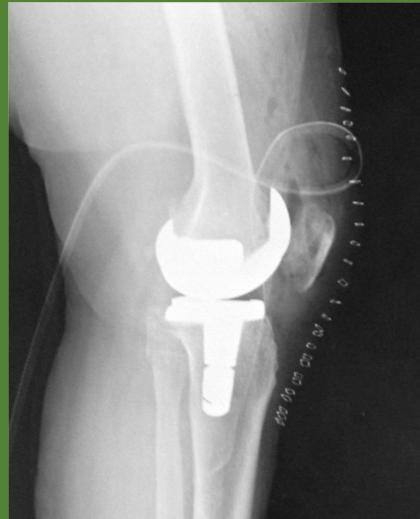

- ✓ Prosthetic joint

- Two weeks before planned Arthroplasty